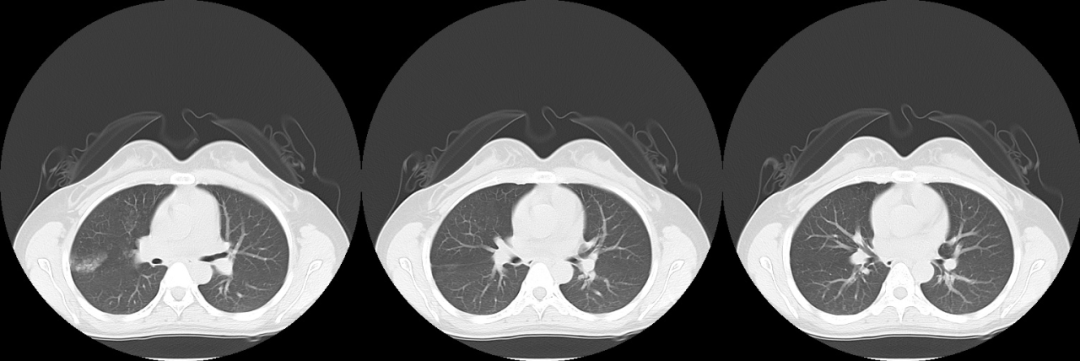

怎么回事,还是和上次一样的地方出现病灶;

这是什么?

各位看官,您认为是什么呢?